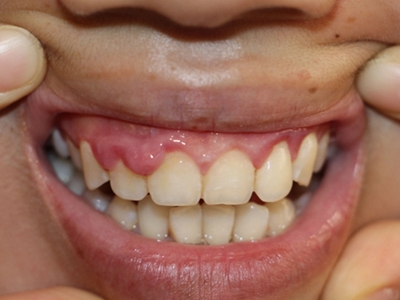

牙龈瘤多发于女性,以青年及中年人为常见,多发生于牙龈乳头部,位于唇、颊侧者较舌、腭侧者多,最常见的部位是前磨牙区。肿块较局限,呈圆形或椭圆形,有时呈分叶状,大小不一,直径由几毫米至数厘米。

肿块有的有蒂,如息肉状;有的无蒂,基底宽广,生长较慢,但在女性妊娠期间可能迅速增大。较大的肿块可以遮盖一部分牙及牙槽突,表面可见牙压痕,易被咬伤而发生溃疡,伴发感染。随着肿块的增长,牙槽骨壁逐渐被破坏,牙可能发生松动、移位。

局部刺激因素,包括菌斑、牙石、食物嵌塞或不良修复体的刺激,引起局部长期慢性炎症,致使牙龈结缔组织形成反应性增生物,即牙龈瘤。此外,牙龈瘤可能和内分泌有关,妇女怀孕期间容易发生牙龈瘤,而分娩后会缩小或停止生长。